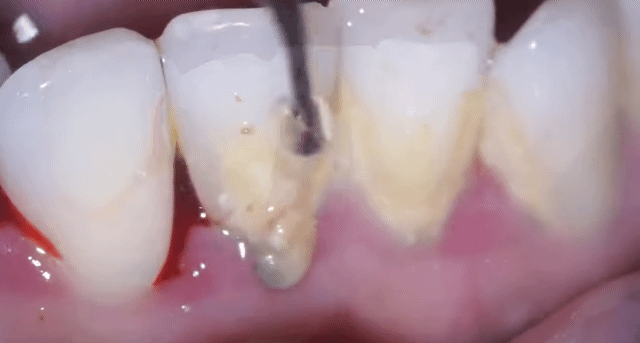

[스크랩] [흥미돋]■ 치과 스케일링 ( 치석 제거)

• 답댓글 작성자야구좋아 | 작성시간 25.03.13 까맣쿤 아니? 아닌 거 같던데! 치석 떼고 나면 잇몸이 부어있어서 그런 욱신거리는 통증?은 조금 있을 수 있어도 치석 많아서 스케일링 할 때 더 아프다는 얘기는 첨 들어봐! 보통 다 못느껴! 치석이 뭉탱이로 떨어지면 그거 막 혀에 닿거나 목구멍에 닿아서 케곅 거리는 사람은 있어...

• 작성자한능검타파 | 작성시간 25.03.13 아 재밌어보이는데... 너무 심하셔서 ㅠ 뿌리가 보일거같아서 안타깝ㅜ

• 작성자박용희 | 작성시간 25.03.13 저정도면 진짜.. 이가 반 정도 빠진만큼 아프겄어